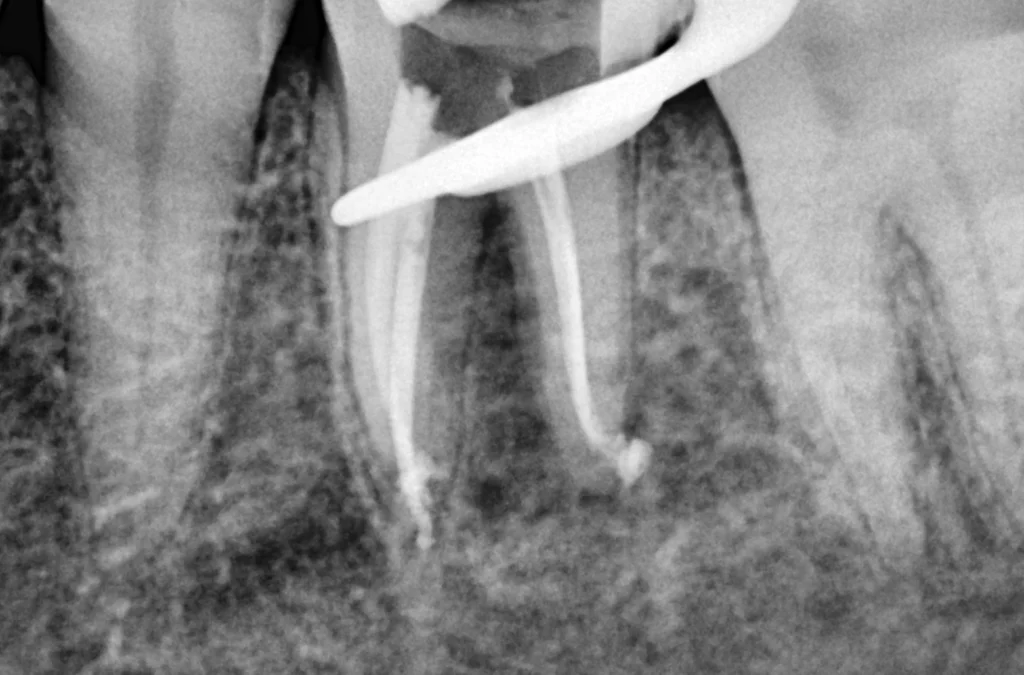

Root Canal Therapy in Beirut

Save your natural tooth and eliminate pain with advanced root canal treatment.

Root canal therapy is a highly effective procedure used to treat infected or damaged teeth.

At Smile Avenue, we use modern techniques to remove infection, relieve pain immediately, and preserve your tooth structure whenever possible. This treatment is often the best alternative to extraction and allows you to keep your natural smile for many years.

When do I need a root canal treatment?

You may need a root canal if you experience severe tooth pain, sensitivity to hot or cold, swelling, or pain that appears spontaneously, especially at night. This treatment removes infection and saves the natural tooth.